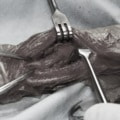

機器

Arthrex社のターゲティングデバイスを用いてピンニングの位置を調整することで、確実な固定を行っています。当院ではこの手術器具以外にも、人の手術にも使用される様々な器具を導入し、手術精度を高め、また医療メーカーと新しい器具の開発、試作にも取り組んでおります。